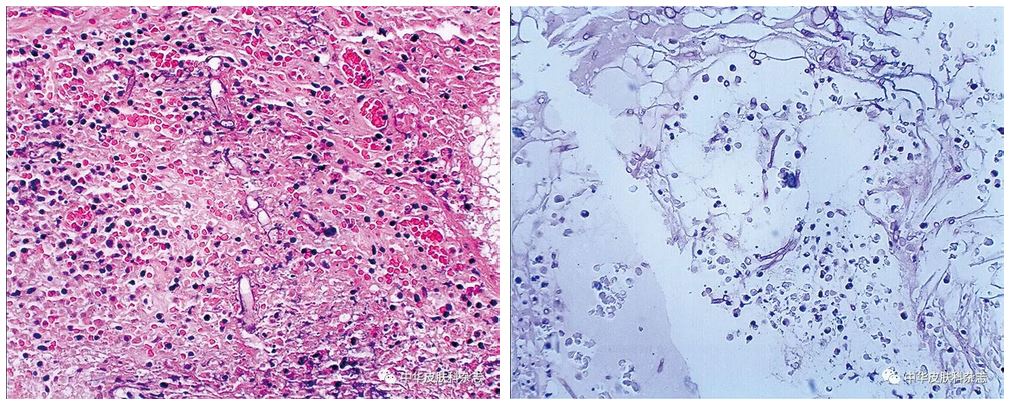

支气管镜活检组织病理显示组织炎性坏死,其内见无隔菌丝,菌丝粗大

图2病理显示坏死组织内大量毛霉菌菌丝,并可见菌丝侵袭血管(gms染色及